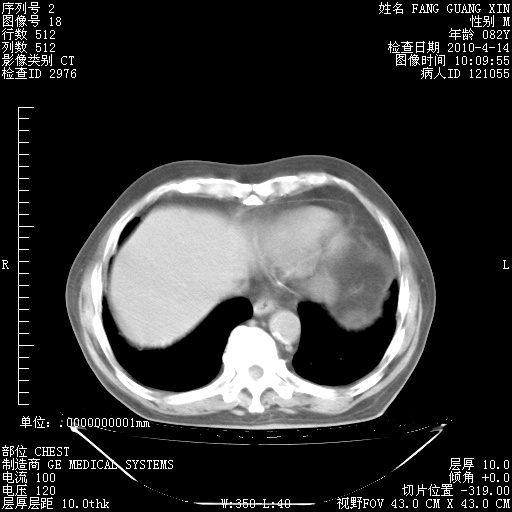

4月14日肺部CT

肺部CT平扫未见异常。